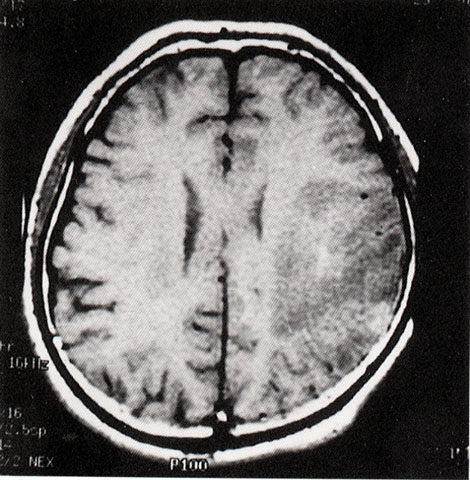

FH1043 脑炎性感染(MRI)

光盘检索编码 FH1043  函授作业图编号 1043

图  名 脑炎性感染(MRI)